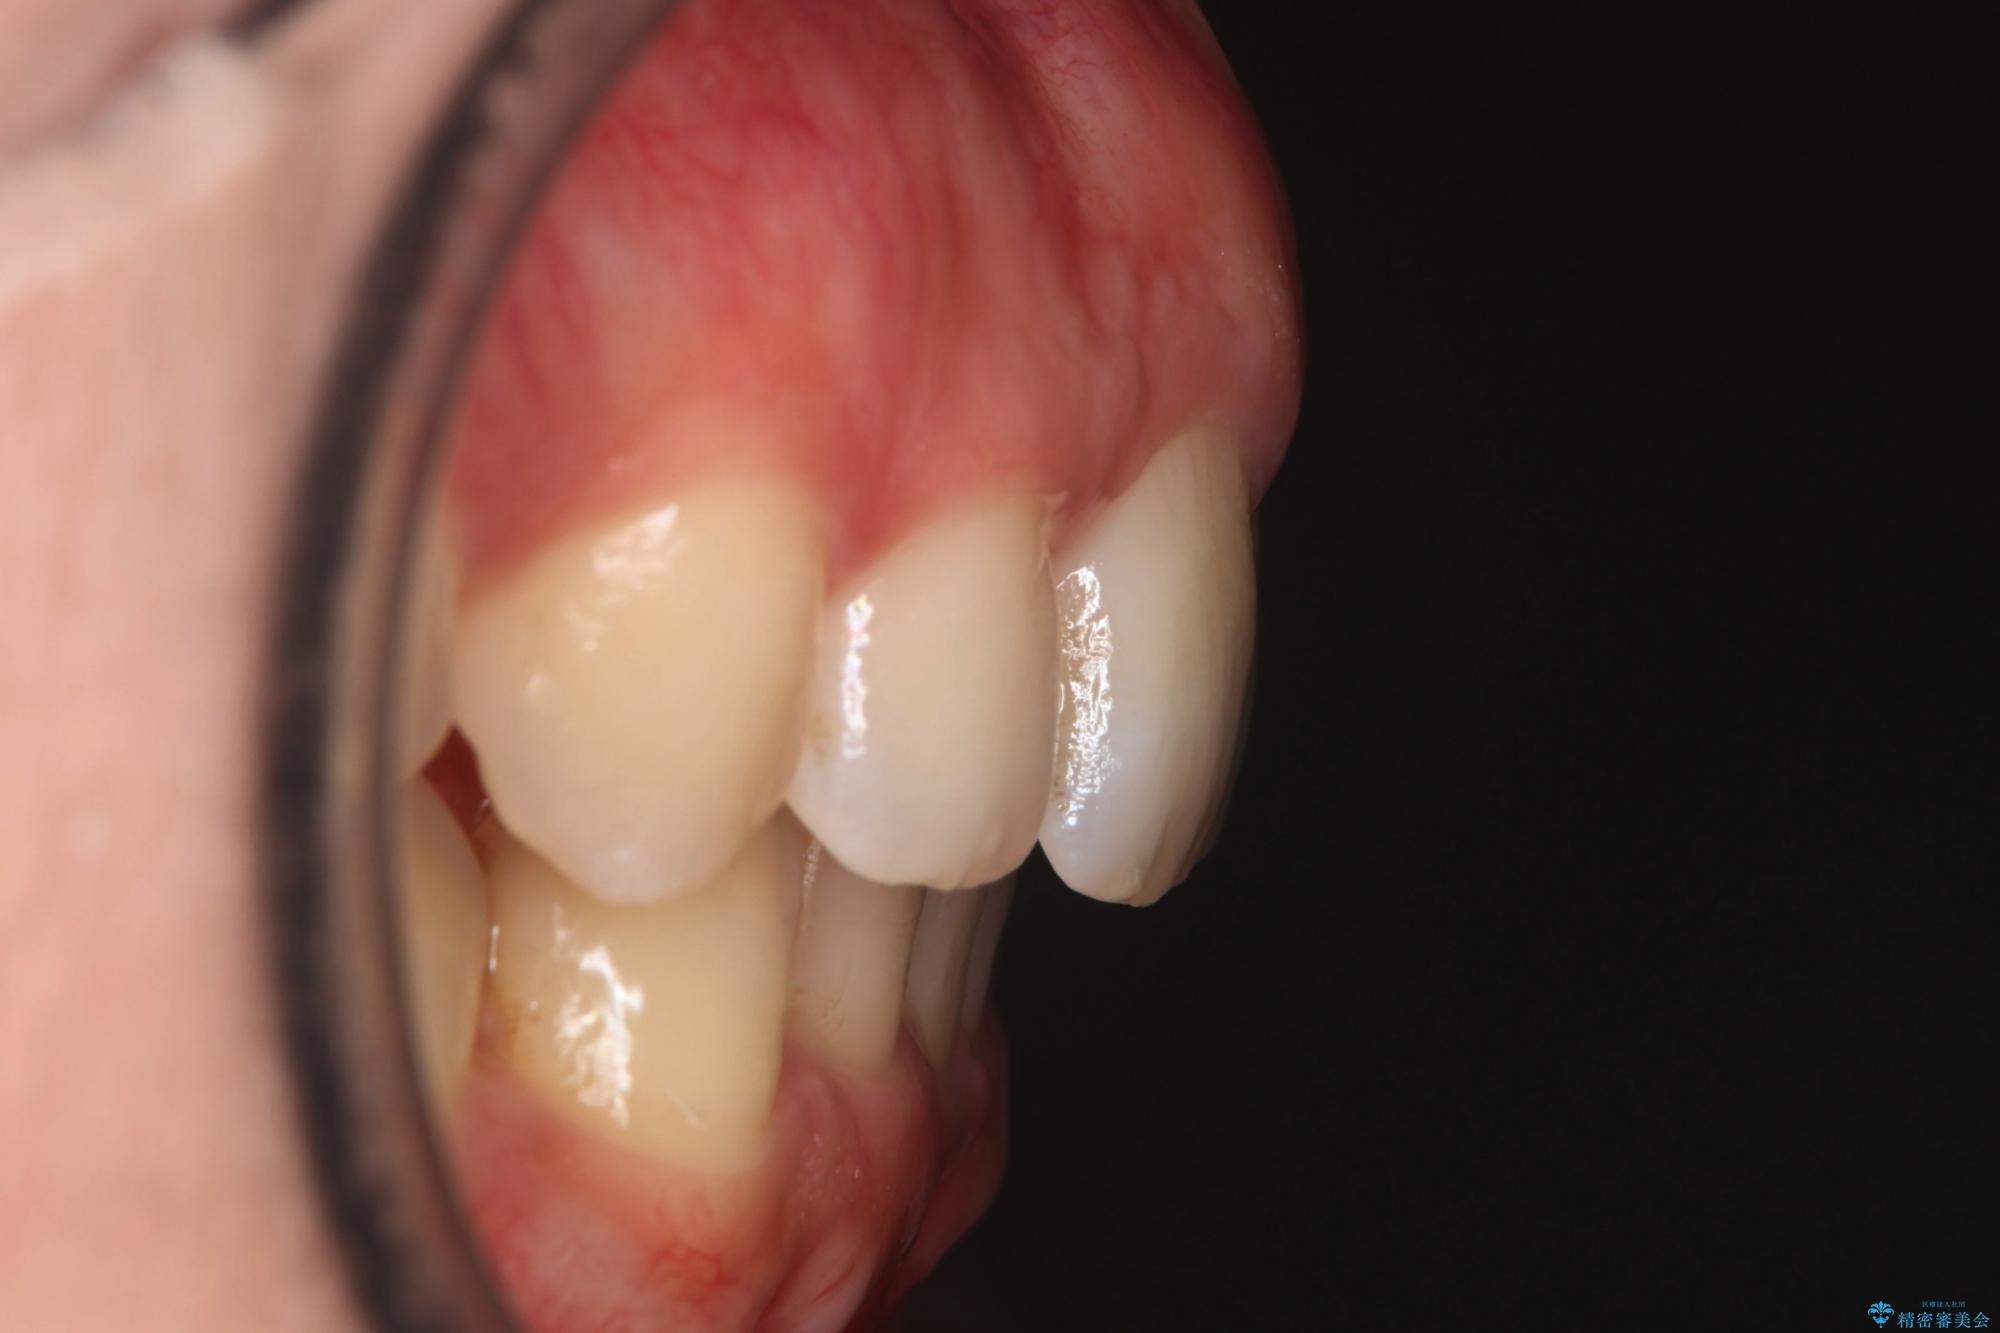

- 下の歯のがたつきを主訴に来院されました。

下の歯のがたつきと右の奥歯の噛みあわせ改善するために治療計画を立てることにしました。

右側臼歯部の咬合改善のために、臼歯部のみ部分的なワイヤー矯正を行い、咬合改善がみられてからインビザラインにて全体的な矯正を行なっていく治療計画を立てました。